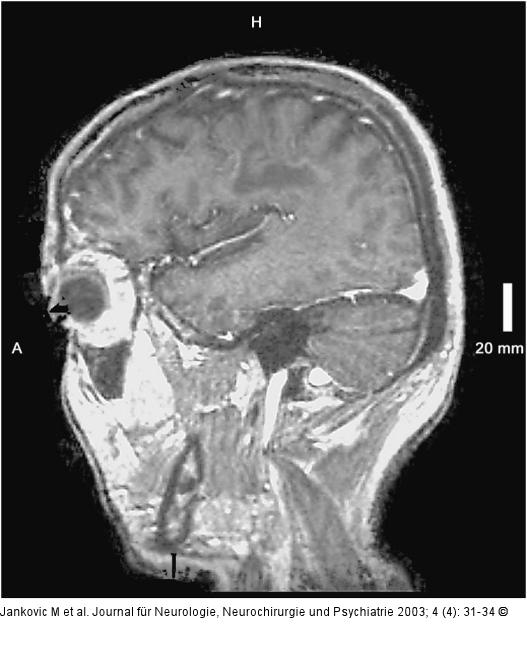

Abbildung 3: Adrenomyeloneuropathie Sagittale T1 des Gehirns mit Kontrastmittel: zarte, randständige Kontrastmittelaufnahme |

Sagittale T1 des Gehirns mit Kontrastmittel: zarte, randständige Kontrastmittelaufnahme |